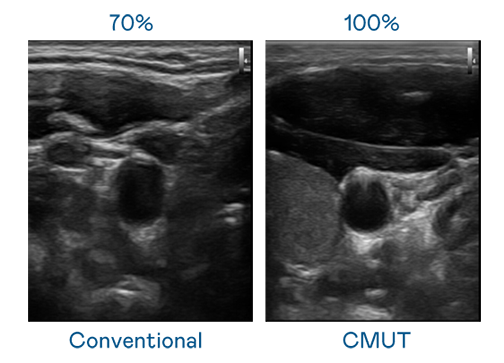

CMUT 技术是一种用电容式微机电元件来产生超音波讯号的技术。与传统 PZT 压电式技术相比,CMUT 频宽增加 30%,更宽频的超音波讯号让影像解析度大幅提升,是实现高影像品质医疗超音波扫描、促进精准医疗发展的关键技术。

超音波影像的解析度高低,首先取决于探头能发出的讯号频宽。304am永利集团 CMUT 可提供高清晰的超音波讯号,提供高频宽、高灵敏度、影像纹理细节更高的超音波影像,协助医护人员缩短影像判读时间及利用精准的医疗影像进行诊断。